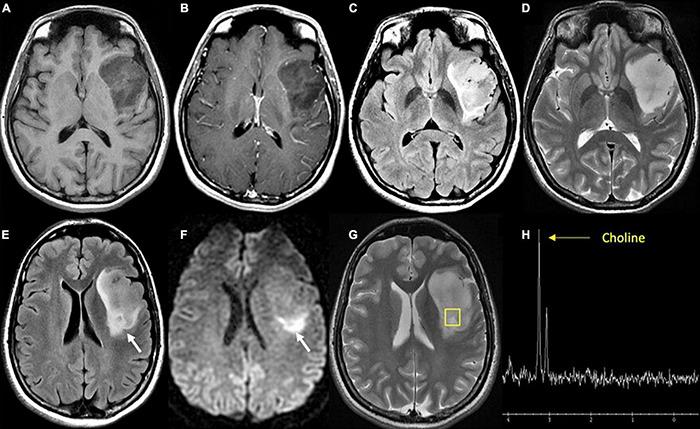

Management of gliomas following initial diagnosis requires thoughtful presurgical planning followed by regular imaging to monitor treatment response and survey for new tumor growth. Traditional MR imaging modalities such as T1 post-contrast and T2-weighted sequences have long been a staple of tumor diagnosis, surgical planning, and post-treatment surveillance. While these sequences remain integral in the management of gliomas, advances in imaging techniques have allowed for a more detailed characterization of tumor characteristics. Advanced MR sequences such as perfusion, diffusion, and susceptibility weighted imaging, as well as PET scans have emerged as valuable tools to inform clinical decision making and provide a non-invasive way to help distinguish between tumor recurrence and pseudoprogression. Furthermore, these advances in imaging have extended to the operating room and assist in making surgical resections safer. Nevertheless, surgery, chemotherapy, and radiation treatment continue to make the interpretation of MR changes difficult for glioma patients. As analytics and machine learning techniques improve, radiomics offers the potential to be more quantitative and personalized in the interpretation of imaging data for gliomas. In this review, we describe the role of these newer imaging modalities during the different stages of management for patients with gliomas, focusing on the pre-operative, post-operative, and surveillance periods. Finally, we discuss radiomics as a means of promoting personalized patient care in the future.

胶质瘤初诊后的管理需要进行周全的术前规划,随后定期进行影像学检查,以监测治疗反应并探查新的肿瘤生长情况。传统的磁共振成像(MR)模式,如T1增强序列和T2加权序列,长期以来一直是肿瘤诊断、手术规划及治疗后监测的主要手段。虽然这些序列在胶质瘤的管理中仍不可或缺,但成像技术的进步使得对肿瘤特征的刻画更加详细。诸如灌注成像、扩散加权成像、磁敏感加权成像等先进的MR序列,以及正电子发射断层显像(PET)扫描,已成为指导临床决策的重要工具,并提供了一种非侵入性方法,有助于区分肿瘤复发和假性进展。此外,这些成像技术的进步已延伸至手术室,有助于使手术切除更安全。尽管如此,手术、化疗和放疗仍使胶质瘤患者的MR图像变化解读变得困难。随着分析和机器学习技术的进步,放射组学在解读胶质瘤成像数据方面具有实现更具定量性和个性化的潜力。在本综述中,我们描述了这些更新的成像模式在胶质瘤患者不同管理阶段的作用,重点关注术前、术后及监测期。最后,我们讨论放射组学作为未来促进个性化患者护理的一种手段。